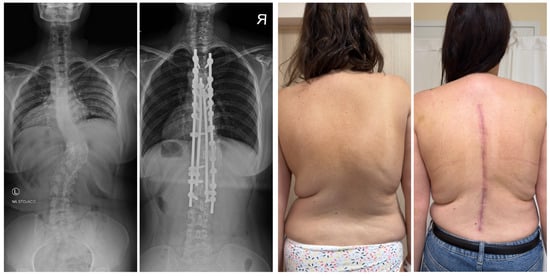

7.3.3. Hemivertebrectomy

8. Complications and Risk Management